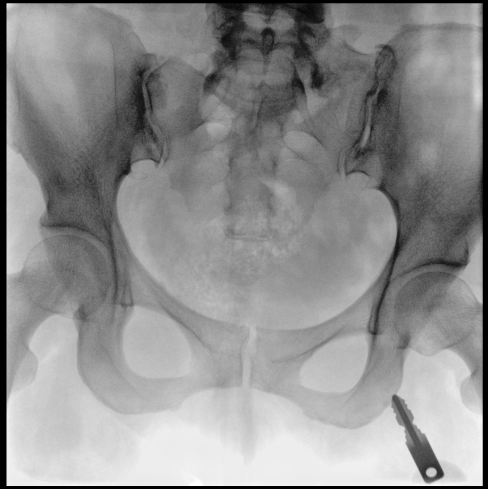

平板尺寸升級 呈現(xiàn)更多解剖細節(jié)

采用30CM×30CM大尺寸動態(tài)平板探測器,成像面積較傳統(tǒng)平板探測器大幅提升。

圖像清晰細膩

高清像素,低信噪比,細小的組織結構也可以清晰顯示。

Clinical picture

臨床圖片